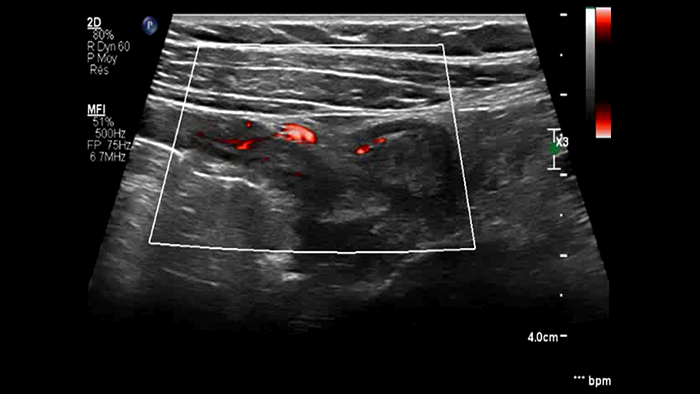

Ces images précises des lésions des couches pariétales forment la base de l’interprétation des changements induits par l’inflammation des parois intestinales et par conséquent de la différenciation entre la maladie de Crohn et la rectocolite hémorragique. L’exploration avec la technologie MFI (MicroFlow Imaging) constitue la deuxième étape. Il s’agit de reconnaître l’aspect de l’hypervascularisation induite par des épisodes inflammatoires actifs. La paroi intestinale normale semble comporter peu de microvaisseaux détectables, uniquement à l’interface de la muqueuse et de la sous-muqueuse, et dans le tissu adipeux mésentérique adjacent. Inversement, la paroi inflammatoire présente de nombreux microvaisseaux. La distinction entre les images d’artefacts de mouvement et les microvaisseaux circulants est alors un point essentiel nécessitant un ajustement parfait des paramètres de détection des micro-flux (voir les boucles, diapositive 8). La comparaison des 4 images suivantes de la maladie de Crohn met en évidence des différences claires qui devraient être interprétées comme étant représentatives des différents états inflammatoires. L’image 1 ne comporte aucun vaisseau visible, ce qui correspond probablement à une absence d’activité. L’image 2 présente quelques vaisseaux ; nous pouvons en conclure que cela correspond à une activité modérée. L’image 3 comporte un plus grand nombre de vaisseaux, signe probable d’une activité intense. L’image 4 présente encore plus de vaisseaux de type pulsatile, ce qui évoque probablement une activité très intense.

Les images sont absolument différentes selon l’état inflammatoire. C’est une question de densité, de pulsatilité, mais également de localisation des vaisseaux. C’est l’avantage de la superposition des images de micro-flux à celles des couches pariétales obtenues par échographie haute résolution. Sur les images suivantes, accompagnées des clichés d’IRM correspondants, il semble que dans le premier cas, à savoir une maladie de Crohn d’apparition récente, les vaisseaux soient localisés à la surface de la paroi intestinale, probablement au niveau de la muqueuse. En revanche, dans les autres cas de maladie plus avancée, ils sont également plus visibles à l’intérieur de la sous-muqueuse et dans le tissu adipeux adjacent.